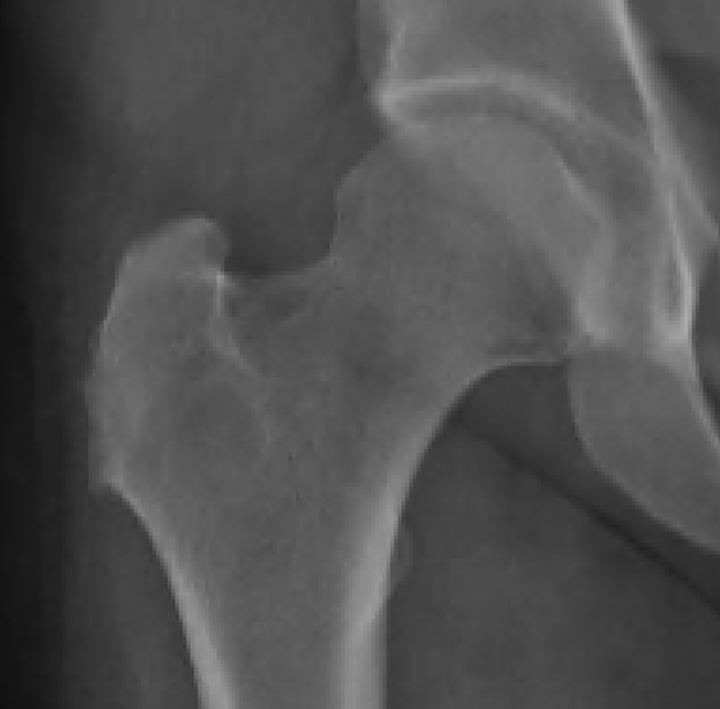

Xray

Greater trochanter cortical irregularities